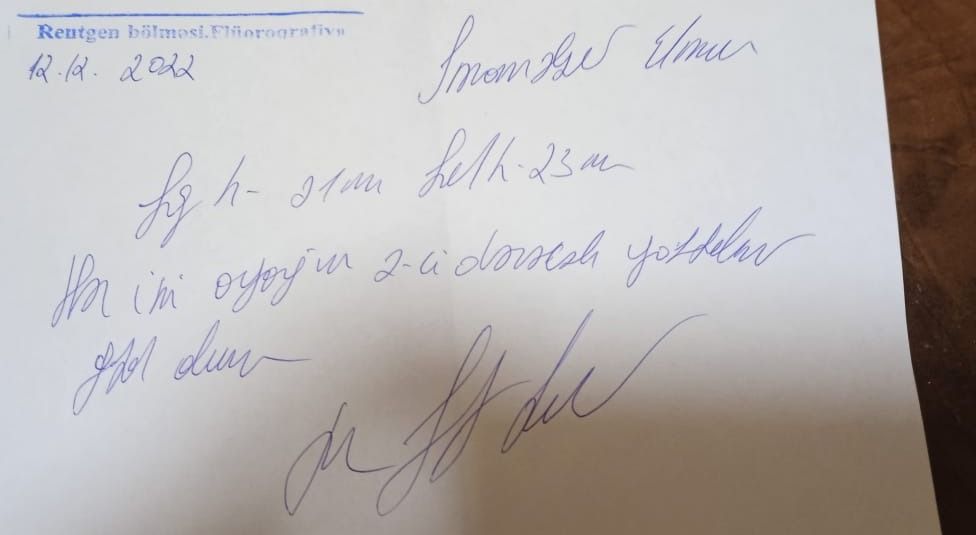

“Oğlum Elman İmaməliyevin ikitərəfli yastıpəncəlik səbəbilə hərbi xidmətə yarasızdır. Bu, Tərtər Rayon Mərkəzi Xəstəxanasından verilən rentgen kağızı ilə təsdiq olunub. Lakin hərbi xidmətə çağırış idarəsinin mayoru oğlumun hərbiyə xidmət üçün yararlı olduğunu əks etdirən saxta sənəd əldə edib. Hansı ki, oğlumun sol ayağı 3-cü, sağ ayağı isə 2-ci dərəcəli ikitərəfli yastıpəncədir.

Hərbi xidmətə çağırış idarəsinin komissiya həkimi rentgen kağızlarını da verib. Amma idarədəki mayor Şahverdiyev uşaqla prinsipə düşdüyü üçün saxta sənəd alıb. O, uşağı təhqir edib, uşaq da deyib ki, səni vuraram. İndi tələb edirəm ki, siz hansı sənədə əsasən müəyyən etmisiz ki, oğlumda hər iki ayağı üçüncü dərəcə yastıpəncədir? Həmin sənədi mənə vermirlər. Deyirlər ki, uşaq yararlıdır, aparırıq. Amma ona verilən möhlət kağızında isə 45-ci və 49-cu maddəyə əsasən, uşağın müalicə almalı olduğu yazılıb”.